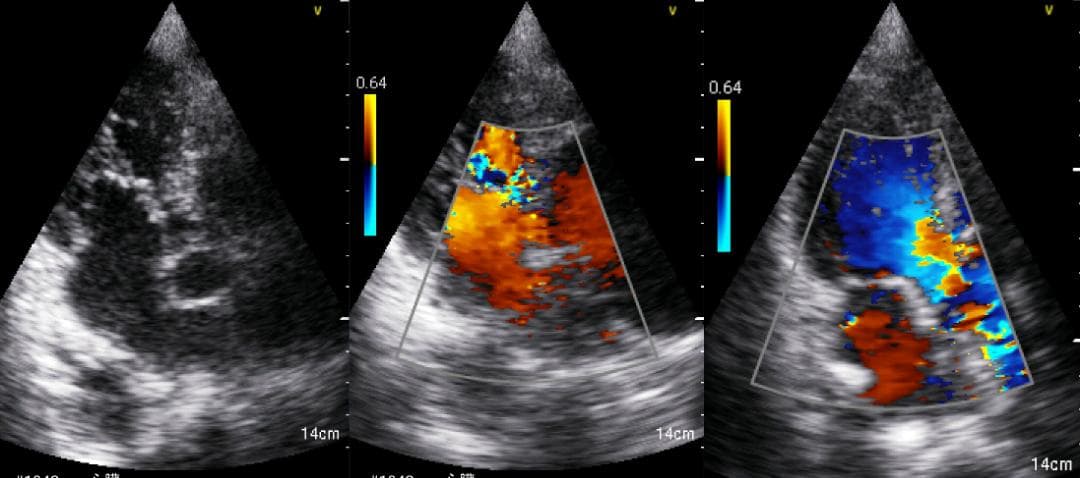

おわかりになる方のみの購入をお願いいたします実際に実施した写真をあげました正常肝臓、胆石症、頸動脈プラーク、同じく頸動脈プラーク、Mrの収縮期、同じくM弁の開放期とA弁の開放期、腹部大動脈瘤、正常の頸動脈、甲状腺右葉の結節、前立腺肥大画像の描出は条件によりますがご検討をお願いいたします経年変化、使用に伴うスレや傷などがあります機能に問題はありませんスキャンは心血管、腹部、体表に対応します外部接続端子のカバーが一部壊れていますが蓋は閉まりますバッテリーはフル充電されますが劣化はあると思います医療用モニタリング機器 Vscan Extend、GE- モデル名: Vscan Extend- ブランド: GE- 色: ホワイト- 機能: 医療用モニタリング機器ご覧いただきありがとうございます。鈴木 ALCARE Youcare-TDc 医療用テープ 25mm 6個。